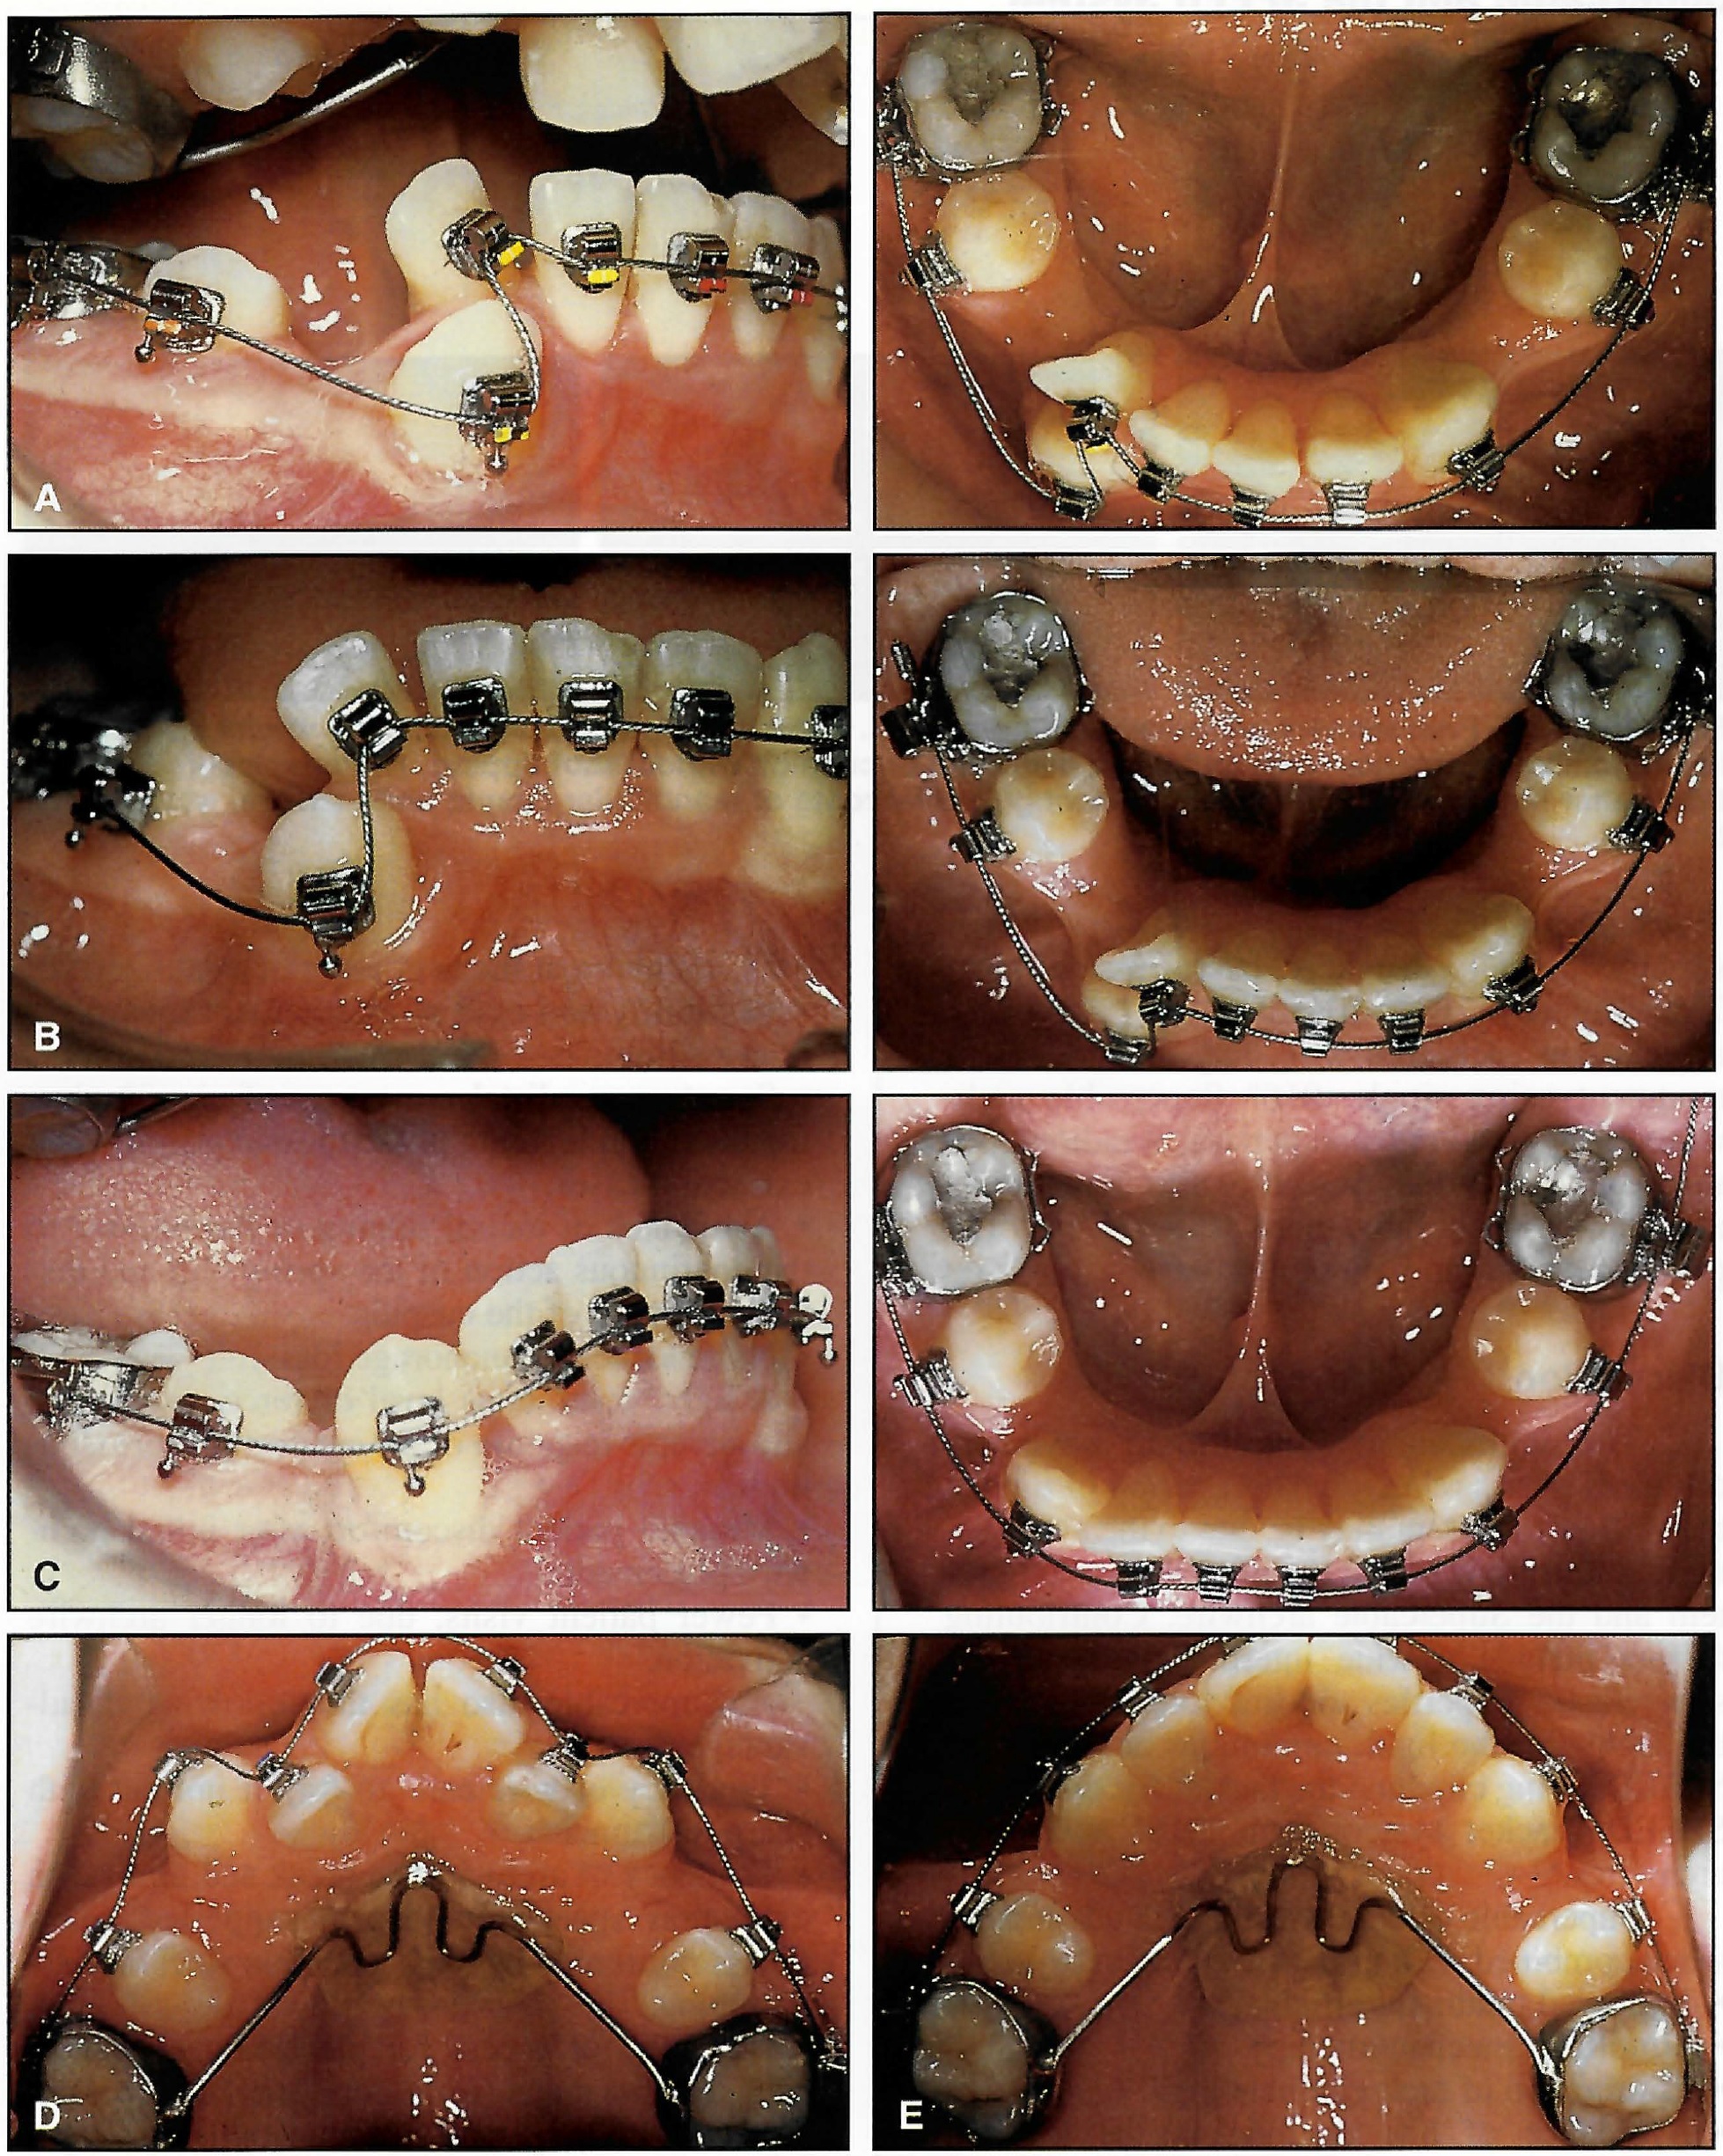

This 12-year-old male patient had severe bimaxillary crowding that necessitated four bicuspid extractions. The mandibular arch had a buccally displaced cuspid and a rotated and slightly lingually displaced lateral incisor (Fig. 7A). Figures 7B-E illustrate the alignment achieved in each arch with only nine weeks of treatment using single .016" Supercable archwires. The panoramic and periapical radiographs showed no root blunting after this remarkable amount of tooth movement (Fig. 7F-H). The patient reported no pain or discomfort.

Fig. 7 12-year-old male with severe bimaxillary crowding and four first bicuspid extractions. A. Initial engagement of mandibular .01611 Supercable. B. Two weeks later, showing initial incisal and cuspid alignment. Note 2mm of excess wire distal to terminal molar bracket. C. Seven weeks later, showing absence of incisor flaring. Note 10mm of archwire distal to molar bracket attachment after closure of extraction spaces. D. Initial engagement of maxillary .01611 Supercable. E. Incisor alignment nine weeks later. Note distal movement of cuspids and closure of extraction spaces without any mesial migration of posterior teeth (continued in next image).

Fig. 7 (cont.) F. Pretreatment panoramic radiograph. G. Panoramic radiograph taken nine weeks later, showing alignment of anterior teeth and distal migration of cuspids without root tipping. H. Periapical radiograph taken after nine weeks of treatment, showing parallel roots of mandibular cuspid and incisors, with no root blunting.